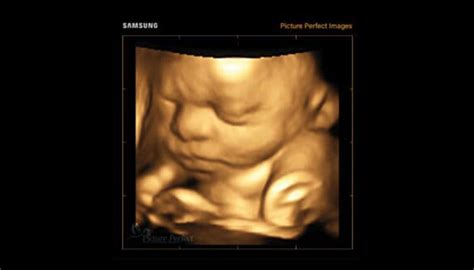

De obicei, sexul bebelușului este determinat la ecografie, în cadrul consultului de rutină din perioada 18-20 săptămâni. Asta înseamnă undeva la jumătatea trimestrului 2 de sarcină, când fătul crește într-un ritm rapid și organele genitale sunt mai bine dezvoltate. Totuși, există tehnici de ecografie avansate care permit aflarea sexului copilului încă de la 14-16 săptămâni. Cu cât sarcina este mai avansată, cu atât medicul poate confirma cu o mai mare precizie sexul.

După săptămâna 20, sexul copilului poate fi confirmat cel mai adesea cu o acuratețe de 95-99% în cadrul morfologiei de trimestru 2. Această ecografie oferă o vizualizare detaliată a fătului.